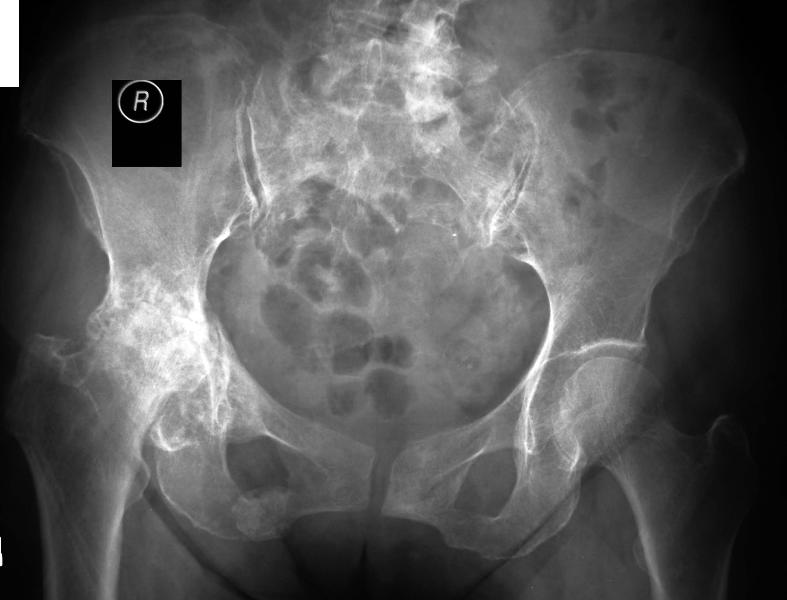

This is a patient who has hip osteoarthritis after a fracture involving the socket many years ago.